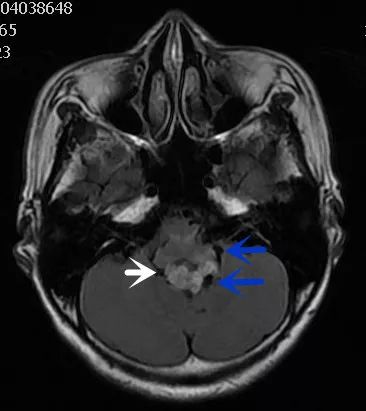

FLAIR图及T1矢状位增强:白色箭头所示小脑延髓池内可见实性占位病变,形态不规则,呈分叶状,病变边界清晰,边缘见血管流空信号影如蓝色箭头所示。

影像描述:小脑延髓池内见不规则异常信号影,呈等及稍长T1长T2信号,内部信号不均,边缘见稍粗大流空信号血管影,FLAIR病灶中心少许片状低信号,增强呈明显强化,DWI不均低信号,ADC不均高信号。小脑半球、延髓、第四脑室受压变形。临近延髓受压变窄,呈长T1长T2信号。